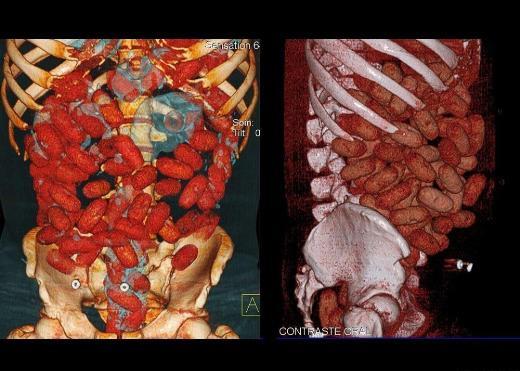

8. Bu CAT scan görüntüsü ise Brezilya'nın Sao Paulo kentindeki Congonhas Havalimanı'nda yakalanan İrlandalı bir erkeğe ait. Karın bölgesinden alınan bu görüntülerde kapsüllere doldurulmuş 830 gram kokain bulunuyor.

Bu CAT scan görüntüsü ise Brezilya'nın Sao Paulo kentindeki Congonhas Havalimanı'nda yakalanan İrlandalı bir erkeğe ait. Karın bölgesinden alınan bu görüntülerde kapsüllere doldurulmuş 830 gram kokain bulunuyor.